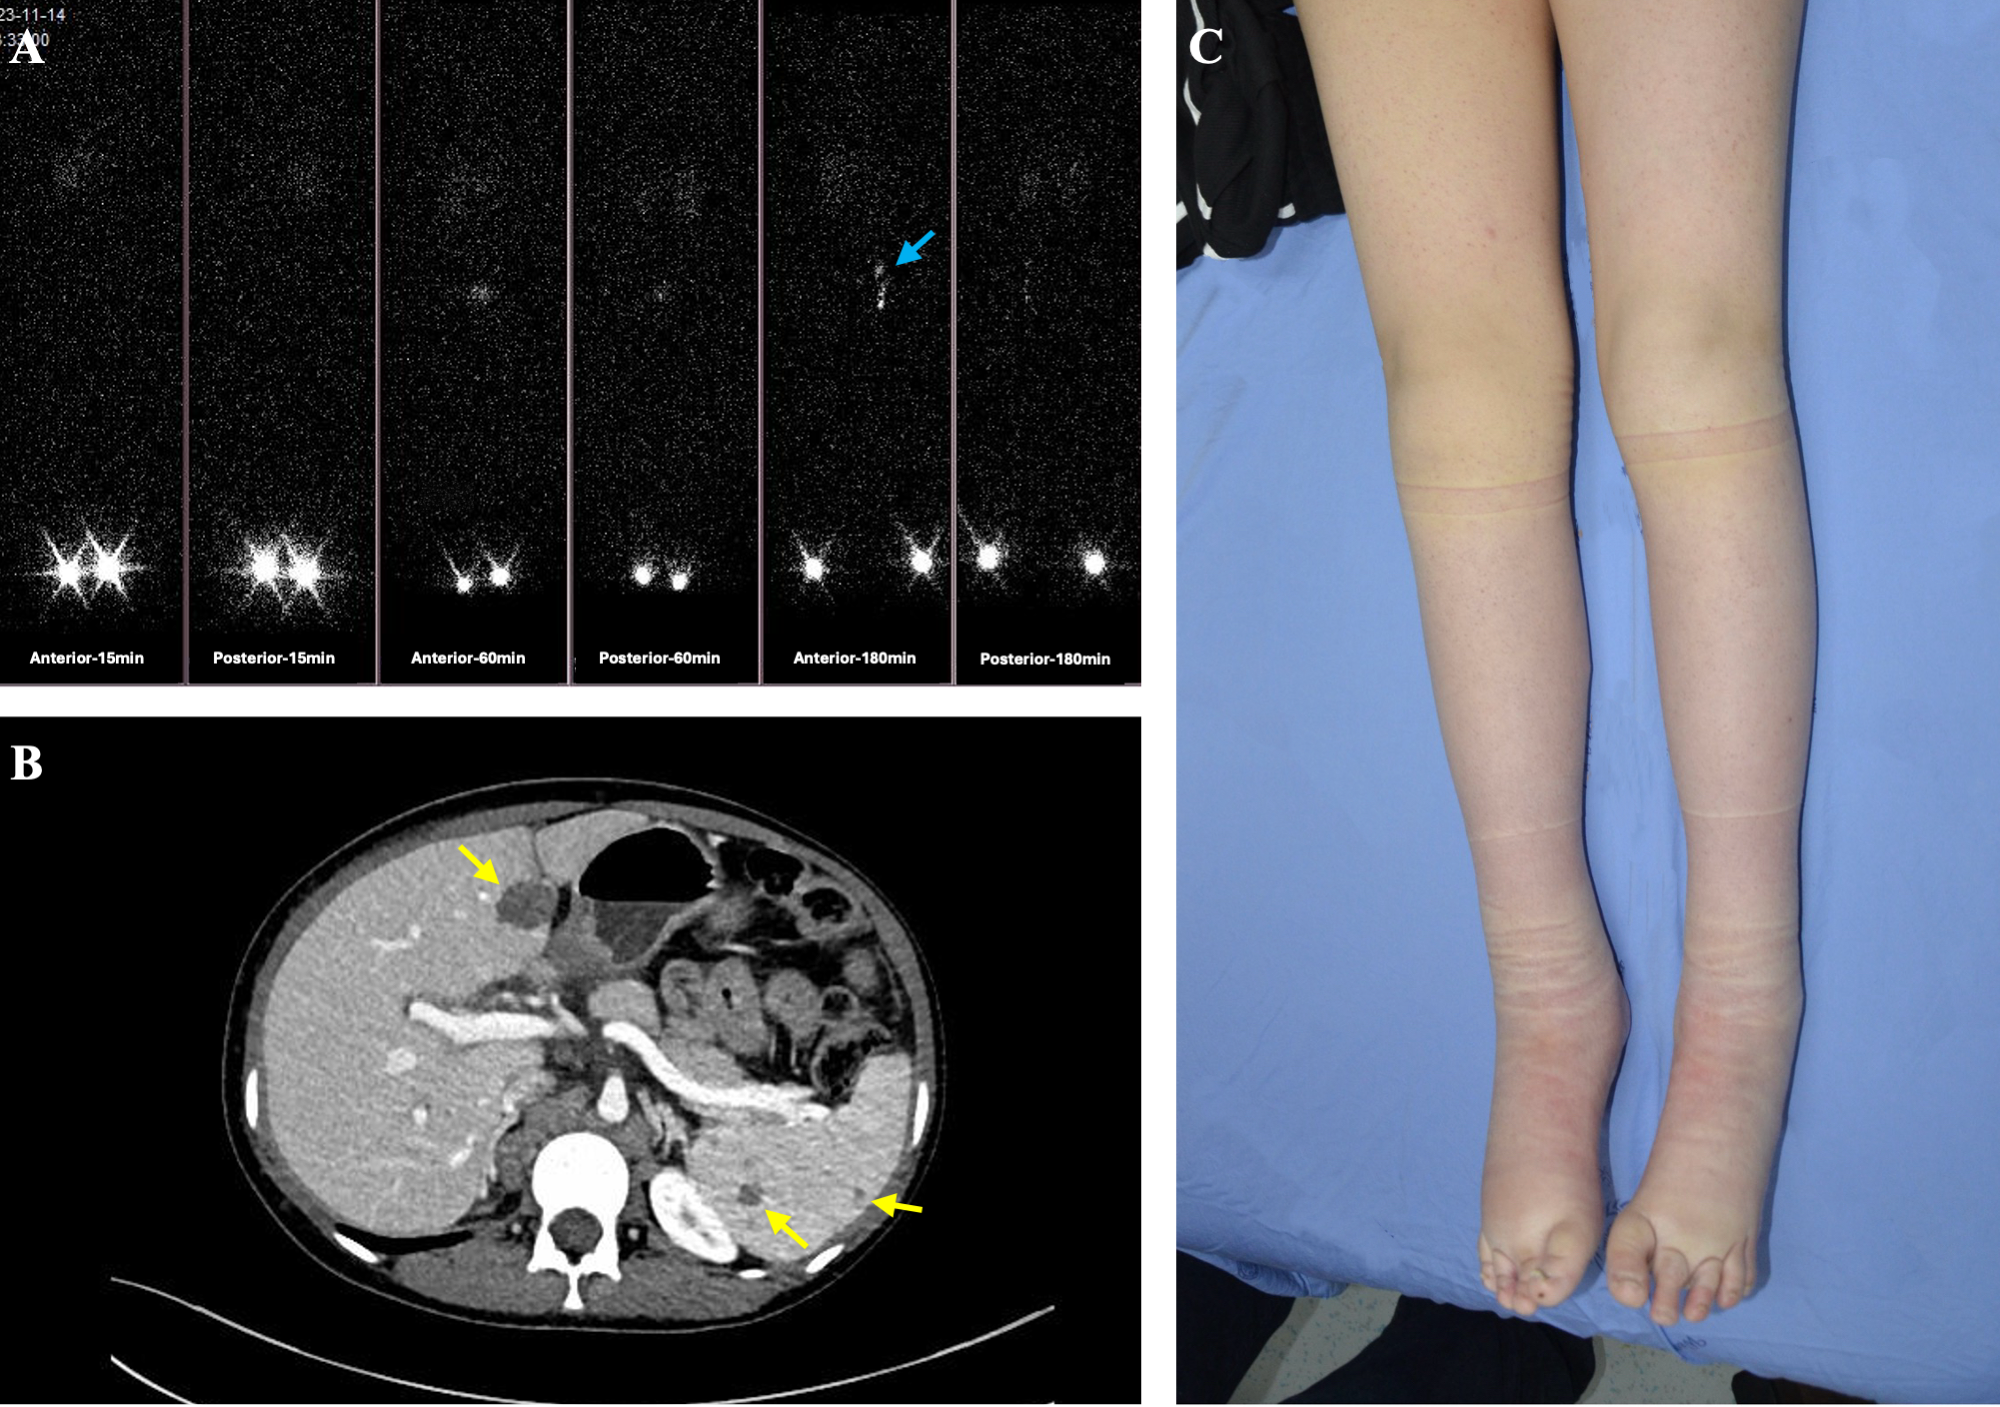

A 13-year-old female presented with bilateral lower limb edema and persistent steatorrhea at birth (Figure 3). At age 3, she was diagnosed with primary lymphedema (PLE) and intestinal lymphangiectasia. Her lymphedema was managed with compression therapy using elastic bandages, while a medium-chain triglyceride (MCT) diet effectively resolved her steatorrhea. At age 11, she began experiencing intermittent right upper abdominal pain, which gradually increased in frequency and duration. No one else in her family has experienced similar symptoms.

Figure 3. A female patient with generalized lymphatic anomaly (GLA) manifested multifocal cystic lesions in the liver and spleen, accompanied by bilateral lower extremity lymphedema. (A) Lymphoscintigraphy shows non-visualization of the right inguinal lymph nodes and delayed, faint visualization of the left inguinal lymph nodes at 15, 60, and 180 minutes post-injection in both feet (blue arrows). (B) Abdominal CT demonstrates multiple well-circumscribed, round hypodense lesions in the liver and spleen (yellow arrows). (C) Clinical photograph reveals extensive bilateral lower extremity swelling, more pronounced on the right, with localized skin thickening and textural changes.

Upon referral to our medical center, MRI identified multiple lymphatic malformations in the liver and spleen. Lymphoscintigraphy further revealed lymphatic drainage obstruction in the right lower limb and significant slowing in the left lower limb. Clinically, the presence of bilateral lower limb edema since birth, along with persistent steatorrhea aligns with the complex and multisystem nature of GLA. Imaging studies further corroborated this diagnosis: MRI revealed multiple lymphatic malformations in the liver and spleen, while lymphoscintigraphy demonstrated lymphatic drainage obstruction in the right lower limb and significant slowing in the left lower limb. These combined clinical and radiological features are characteristic of GLA, confirming the diagnosis. We used ctDNA sequencing to analyze peripheral blood samples from this patient for potential genetic mutations. ctDNA sequencing analysis of the peripheral blood of patient 3 revealed a somatic mutation of NM_006206 (PDGFRA): c.1415T>G (p.I472S), with a mutation abundance of 49.56%. A lymphedema specialist was consulted, and physical therapy techniques were introduced. However, despite these interventions, her PLE and abdominal pain showed only slight improvement. Similar symptoms or gene mutations were not identified in the family of Patient 3.